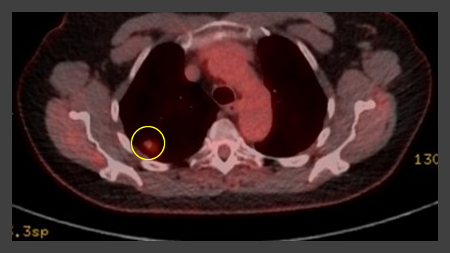

[Figure caption and citation for the preceding image starts]: PET-CT com 18-fluordesoxiglucose (18-FDG) mostrando baixa captação em lesão semissólida posterior no lobo superior direito. A ressecção cirúrgica confirmou adenocarcinoma com padrão primariamente lepídicoDo acervo de Dr. George Tsaknis, MD, PhD, FRCP (Londres), MRQA, MAcadMEd, PGCert; usado com permissão [Citation ends].